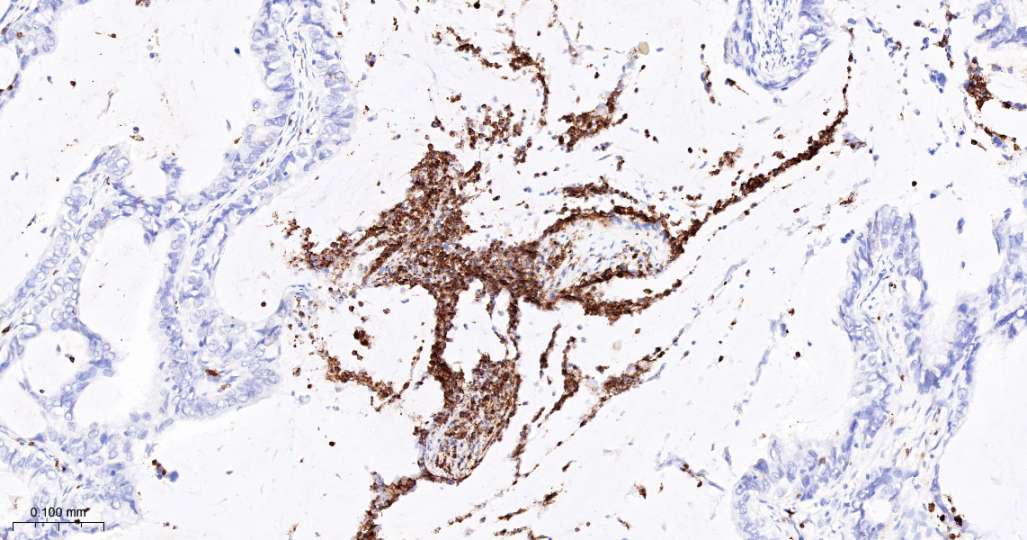

Immunohistochemical analysis of paraffin embedded Human kidney tissue slide using IHC0686H (Human FUT4 Kit).

Immunohistochemical analysis of paraffin embedded Human spleen tissue slide using IHC0686H (Human FUT4 Kit).

Immunohistochemical analysis of paraffin embedded Human lymph nodes tissue slide using IHC0686H (Human FUT4 Kit).

Immunohistochemical analysis of paraffin embedded Human lung cancer tissue slide using IHC0686H (Human FUT4 Kit).

Immunohistochemical analysis of paraffin embedded Human endometrial carcinoma tissue slide using IHC0686H (Human FUT4 Kit).

Immunohistochemical analysis of paraffin embedded Human placenta tissue slide using IHC0686H (Human FUT4 Kit).